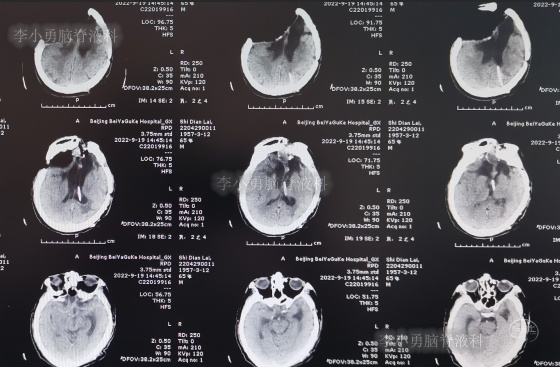

为求进一步治疗,2022年4月29日,第2次来李小勇脑脊液科治疗。入院时:意识不清,刺痛后四肢能动(图-31),查头颅CT(图-32)示脑室有扩张,有积气。

图-32:2022年4月29日头颅CT

入院后当天进行了原分流管拔除术+脑室引流术,术后当天查头颅CT示有出血(图-33)。

图-33:2022年4月29日术后头颅CT

术后5天即2022年5月3日,查头颅CT示脑室有缩小(图-35)。

图-35:2022年5月3日头颅CT

2022年5月13日(入院治疗15天),查头颅CT示脑室又有缩小(图-36)。

图-36:2022年5月13日头颅CT

2022年5月23日(入院治疗25天),查头颅CT示脑室缩小(图-37)。

图-37:2022年5月23日头颅CT

脑脊液化验变正常后于2022年9月9日(治疗133天),进行了脑室腹腔分流术(图-39)。

图-39:2022年9月9日头颅CT

2022年9月23日(李小勇脑脊液科治疗147天)出院,出院时:意识清楚,肢体活动、走路正常,住院期间脑脊液未见漏(图-40);出院前头颅CT示颅骨缺损(图-41)。

图-41:2022年9月19日出院前头颅CT